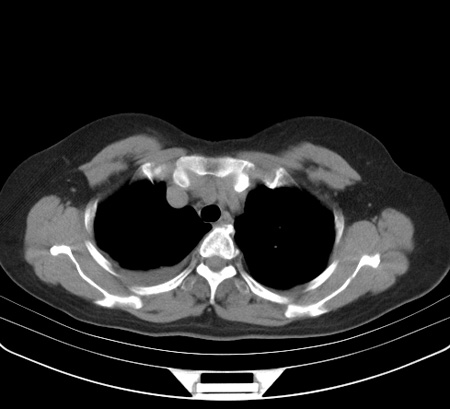

以下是引用余辉在2009-2-19 20:10:00的发言:[br]多考虑急性感染性病变,右中叶尚可见多枚小斑片状影,多为化脓性肺炎,双侧胸腔积液

以下是引用随光逐影在2009-2-19 20:33:00的发言:[br]1)考虑右肺炎症;建议抗炎治疗后复查。2)双侧胸腔积液(以右侧为甚)。

以下是引用花凤凰在2009-2-19 20:46:00的发言:[br]病人有发热,胸痛急性起病,主要病变位于右肺中叶外侧段,呈楔行改变,位于外带胸膜下,考虑为肺梗塞可能!!!!!!!!!!!!!!!!!!!!!!!!!!!!!!!!!!!